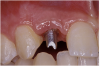

The 3.7-mm diameter Tapered Screw-Vent implant drilling sequence required three drills: pilot, intermediate, and final sizing. Thus, three separate templates were fabricated to accommodate these sizes. The templates were removed easily and replaced with the next sequential size in less time than it takes to change the drill on the surgical handpiece. After the osteotomies had been completed, the implants were delivered to the site (Figure 16A and Figure 16B). For this internal hex connection implant, the author r.commends that the flat of the antirotational hex be positioned to the facial for proper orientation of the restorative components (Figure 17A). Preprepared margins were created from a milled titanium fixture mount transfer post, which was delivered to the implant as support for an immediate transitional restoration. The facial “dot” helped confirm the orientation of the abutment to the facially positioned flat side of the internal hex connection (Figure 17B). Before cementation of the transitional acrylic restorations, a closed-tray, fixture-level impression was made, and a soft-tissue model fabricated.

Figure 16a  After (A) the osteotomies were completed, (B) the implants were placed.

Figure 16a

Figure 16b  After (A) the osteotomies were completed, (B) the implants were placed.

Figure 16b